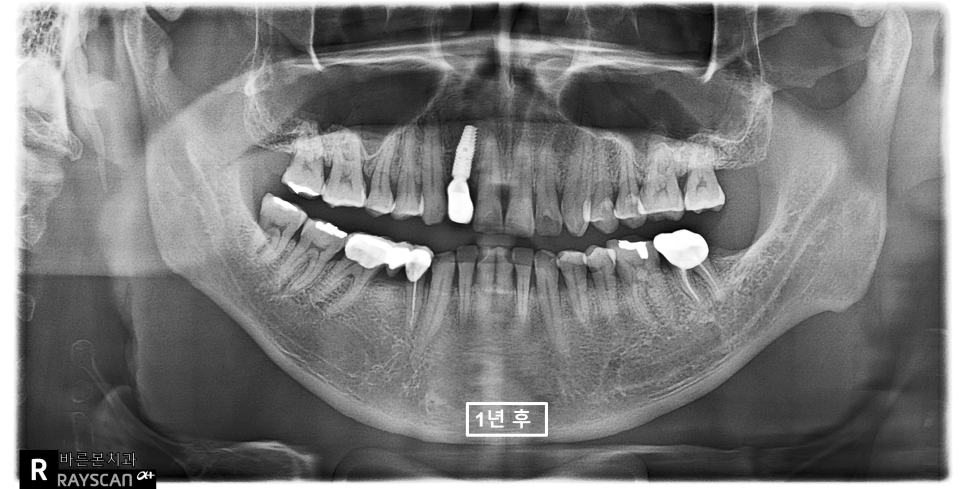

24.05.20 (정기검진) – 55y 김OO님

치료 후 1년동안

매교역치과에서

꾸준하게 검진 및 잇몸관리를 받으셨고

다른 치아들에는 아직 별탈없이

잘 지내고 계십니다 ^^